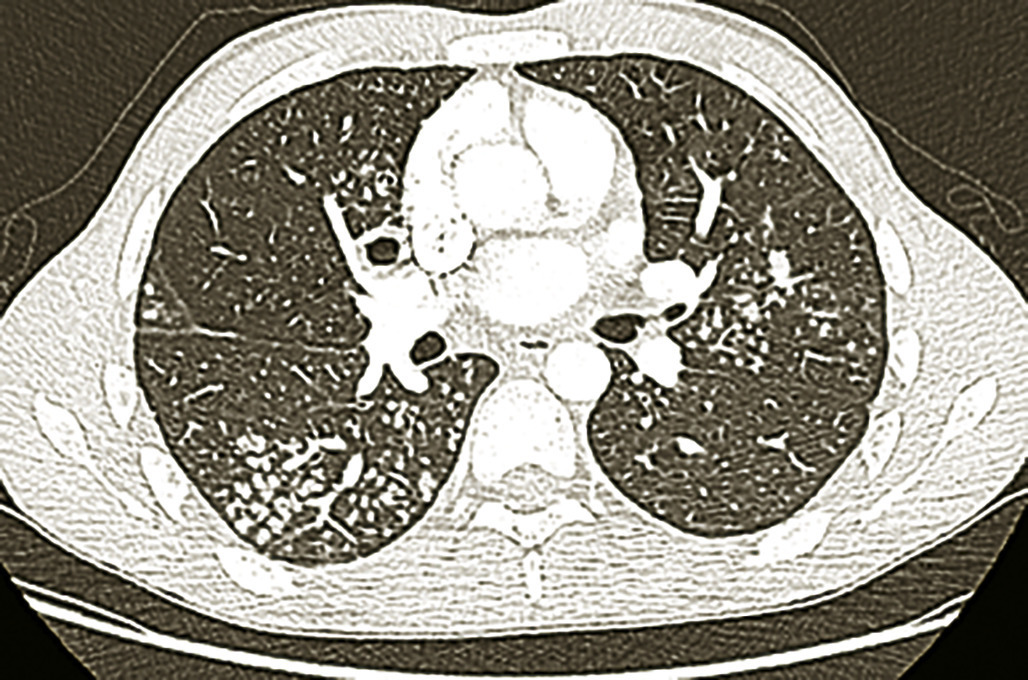

Imagerie (fig.1-4)

L’imagerie thoracique (radiographie, tomodensitométrie plus précise) révèle des opacités et modifications morphologiques de plusieurs types ± associées : atteintes bronchiolaires, bronchocèles, nodules acinaires, masses ± excavées, formes pneumoniques, rétractions lobaires, adénopathies médiastinales, pleurésies, miliaires.